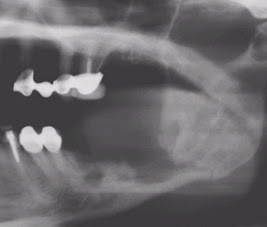

Figura 2. Imagen de una persona con periodontitis crónica avanzada

1. Necrosis maxilo-mandibular asociada al uso de bisfosfonatos

Los bisfosfonatos son medicamentos utilizados en el tratamiento de la hipercalcemia maligna, complicaciones esqueléticas asociadas a enfermedades metastásicas del hueso, enfermedad de Paget's, y osteoporosis. (5) La osteonecrosis de la mandibula es una condición clínica recientemente asociada al uso de bisfosfonatos nitrogenados. Los primeros reportes fueron descritos por el Dr. Robert Marx en el 2003. Clínicamente se observa una exposición del hueso, más frecuentemente en la mandíbula en la zona lingual de los molares. Hay una alta probabilidad de sobreinfección y difícil cicatrización del tejido blando y óseo que lo recubre. El riesgo de desarrollar osteonecrosis asociado a bisfosfonatos oscila entre 1/10,000 a 1/100,000 en pacientes que están en terapia con bisfosfonatos orales. El riesgo es mucho más alto en paciente con cáncer en altas dosis intravenosas, entre el 1% y 10%. (5) El tratamiento es paliativo, requiriendo administración de analgésicos, antibióticos y haciendo lavados antisépticos periódicos del hueso expuesto para prevenir o controlar la sobreinfección y el retiro de los secuestros óseos.

Figura 5. Osteonecrosis mandibular asociado a la ingesta de bisfosfonatos

Figura 6. Radiografía panorámica evidenciando necrosis mandibular.